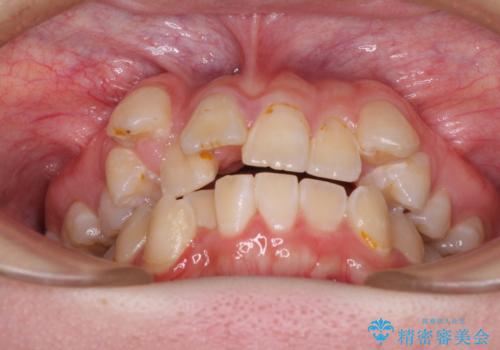

- 前歯のデコボコを気にして来院された患者様です。

前歯のデコボコはもちろん気になるところですが、舌の突出癖により上下の前歯に大きな隙間がある状態でした。

上下前歯が非接触である開咬は、インビザラインによる治療がお勧めではありますが、非抜歯矯正か抜歯矯正か悩む口元であり、途中抜歯矯正に切り替えたときに対応しやすいよう、ワイヤー装置にて治療を行うこととしました。